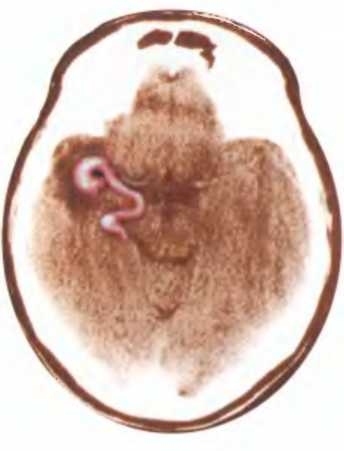

Непосредственная стимуляция височной доли может вызывать сильные эротические ощущения. Разросшиеся кровеносные сосуды, отмеченные кружком на этой томограмме, стимулировали вспышки мозговой активности, которые могли вызывать у пациента оргазм в самое неподходящее время. Эти оргазмы случались у него примерно раз в три недели в течение трех лет, пока их причина не была установлена. [Источник: Reading, J. P., and R.G. Will Unwelcome orgasms // The Lancet 350 (1997). 1746.]